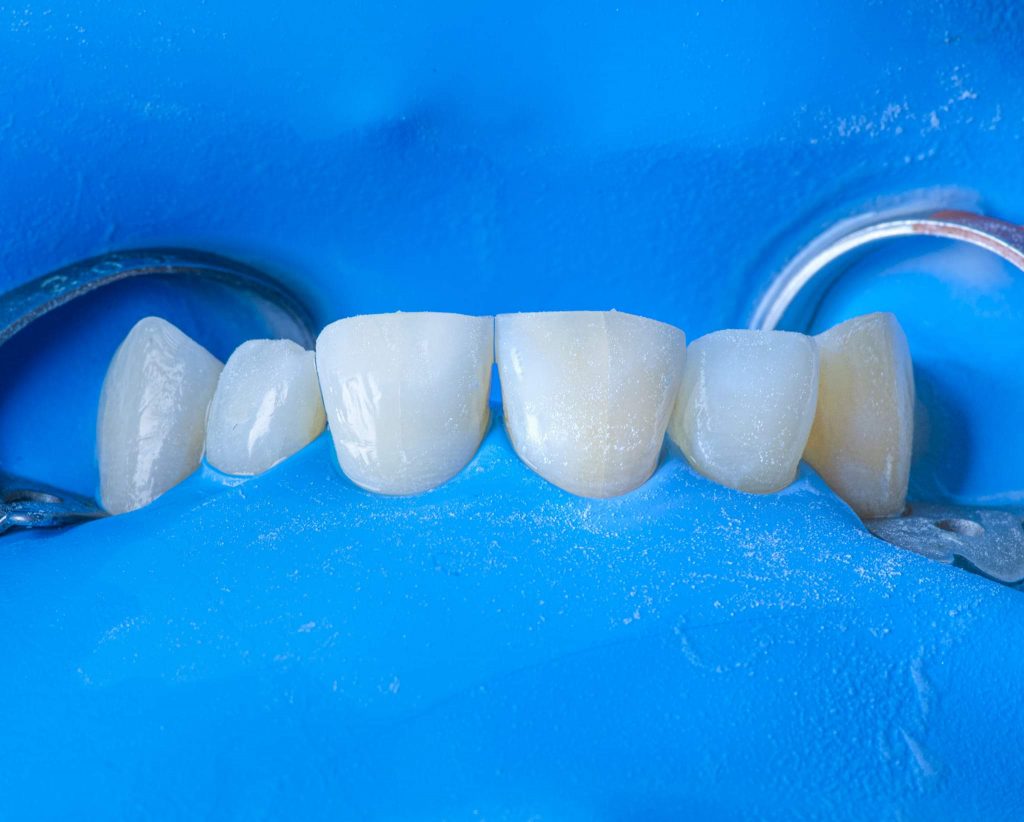

3. Step-by-step clinical procedure

The clinical treatment steps are presented in the images below, with a simple description below each image.

Clinical note: In this case, the wax-up was made only for the central and lateral incisors. However, during the clinical procedure, I noticed that the canines were also needed some correction by composite materials to achieve better morphological shapes, and to provide better smile curve.